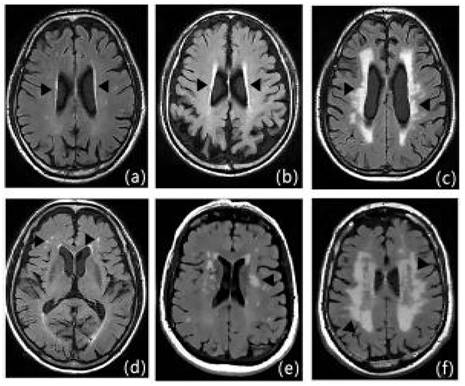

Figure 3

Fazekas scale score: Figures a-c show the paraventricular cerebral white matter, and as a thin layer (1 point), b as a halo (2 points), and c as an extension into the deep white matter (3 points); figures d-f show the deep cerebral white matter, d as a dot (1 point), e as the beginning of fusion (2 points), and f as a large area of fusion (3 points).